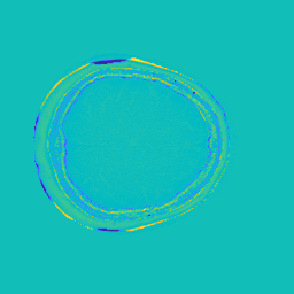

Model-based treatment planning for transcranial ultrasound therapy typically involves mapping the acoustic properties of the skull from an x-ray computed tomography (CT) image of the head. Here, three methods for generating pseudo-CT images from magnetic resonance (MR) images were compared as an alternative to CT. A convolutional neural network (U-Net) was trained on paired MR-CT images to generate pseudo-CT images from either T1-weighted or zero-echo time (ZTE) MR images (denoted tCT and zCT, respectively). A direct mapping from ZTE to pseudo-CT was also implemented (denoted cCT). When comparing the pseudo-CT and ground truth CT images for the test set, the mean absolute error was 133, 83, and 145 Hounsfield units (HU) across the whole head, and 398, 222, and 336 HU within the skull for the tCT, zCT, and cCT images, respectively. Ultrasound simulations were also performed using the generated pseudo-CT images and compared to simulations based on CT. An annular array transducer was used targeting the visual or motor cortex. The mean differences in the simulated focal pressure, focal position, and focal volume were 9.9%, 1.5 mm, and 15.1% for simulations based on the tCT images, 5.7%, 0.6 mm, and 5.7% for the zCT, and 6.7%, 0.9 mm, and 12.1% for the cCT. The improved results for images mapped from ZTE highlight the advantage of using imaging sequences which improve contrast of the skull bone. Overall, these results demonstrate that acoustic simulations based on MR images can give comparable accuracy to those based on CT.